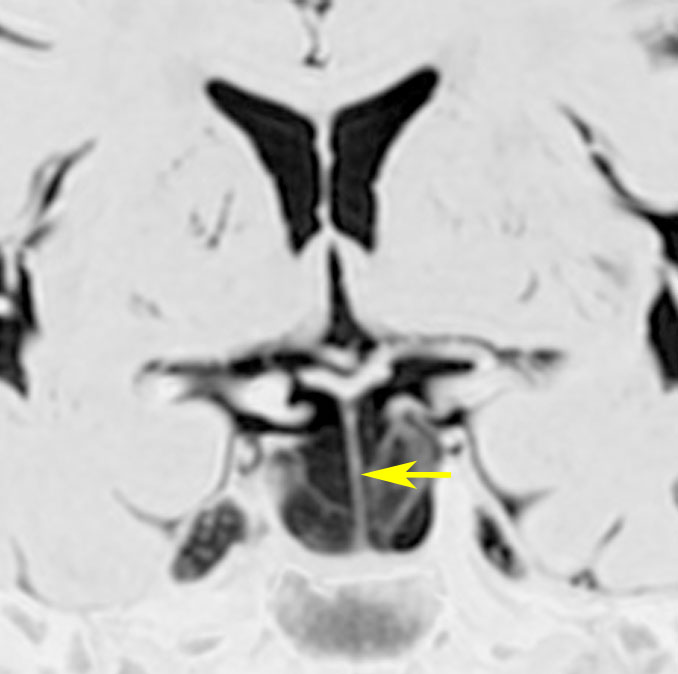

トルコ鞍内くも膜のう胞:先天性無症候性

偶然に発見されたものです,下垂体柄(黄色の矢印)がすごく伸びていて下垂体組織が扁平化していますが,先天性と思われ無症状です。何も治療しないでほっておきます。